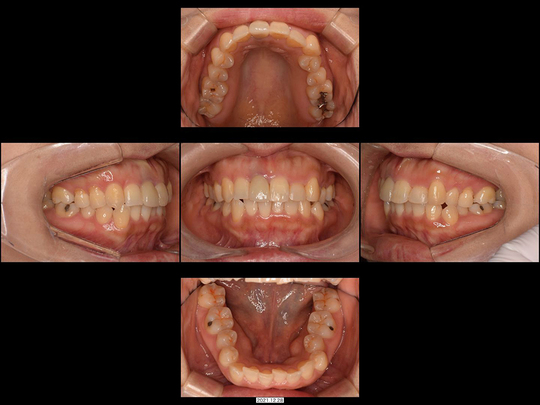

Oさん 40代 女性

矯正前

画像をクリックで拡大

矯正後

治療の説明

上の前歯が磨きづらく、紹介された矯正専門医院に相談したところ、「上の前歯2番目を抜歯して3番目の歯を2番目の形にする」と言われたケースです。

精査の結果、すでに3番目の歯の歯ぐきが下がってきていることから、これを2番目の歯として使った場合、見た目が非常に不自然になる可能性および不必要に削るリスクが高すぎると判断できました。また、唇の形とそのスマイルラインを考慮した結果、通常通りの小臼歯抜歯併用の全体矯正で対応しました。

治療の期間・回数

18か月、20回

​費用

858,000円